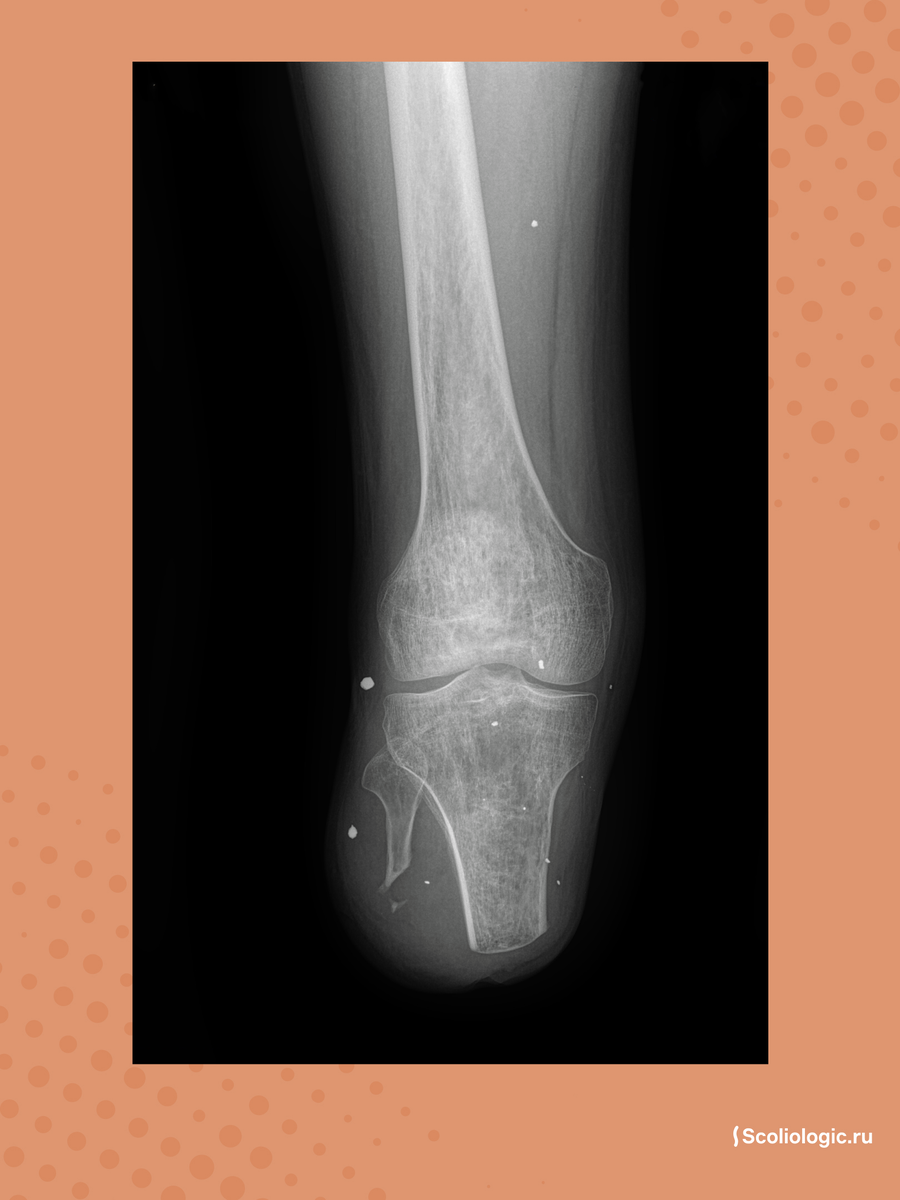

Ногу удалось сохранить, но опираться на неё было невозможно. Стопа застыла в неправильном положении, коленный и голеностопный суставы полностью потеряли подвижность. Рентген показал, что в суставах появились костные конгломераты — плотные образования из сросшихся осколков, которые заблокировали движение. Без опорной ноги делать протез второй было бессмысленно. Пациент передвигался на коляске и очень хотел снова начать ходить.